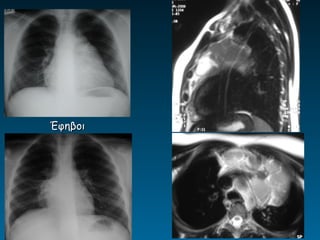

Έφηβοι

• Εναλλακτικά της α/ας ΥΧ       -ΥΤ-ΜΤ